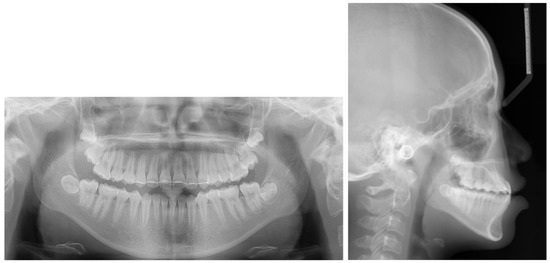

2. Case Presentation

2.1. Diagnosis and Etiology